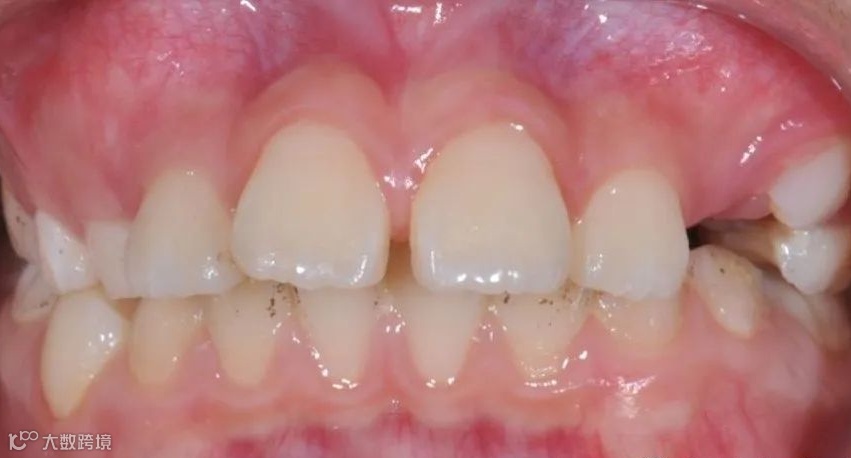

治疗前右侧咬𬌗相

治疗前正面向咬𬌗相

治疗前左侧咬𬌗相